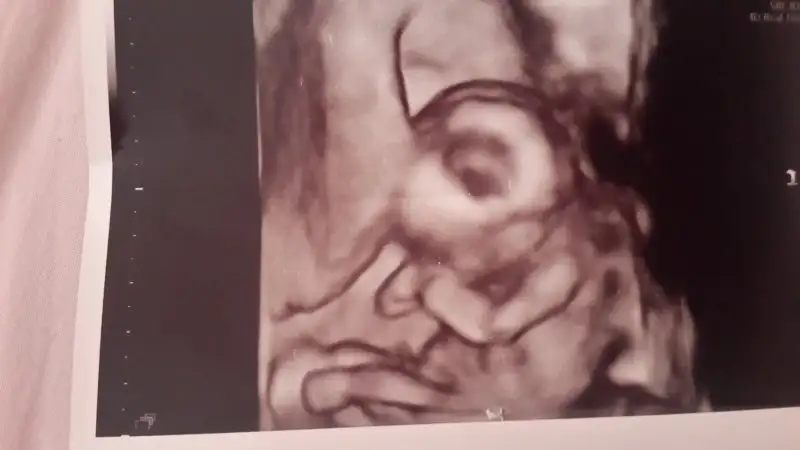

Gunaydın canım negusel bebişini görüceksin bugun.benim önümüzdeki cuma kontrolum ama beklemek cok zor.bide 2 gundur cok bas donmesi yasadığım için acaba bi sorun mu var die dusunmeden edemiyorum Cok dua edicem hepinize inşallah guzel haberler verin.

Cnm daha belli değil her gittiğimizde uyuyor göstermiyor kendini bugün tedbirli geldim kayısı suyu ve bitter çikolata attim ağzıma bi dilim bide armut muz fln yedim uyanık olsun diye bakalim kısmet artık:)